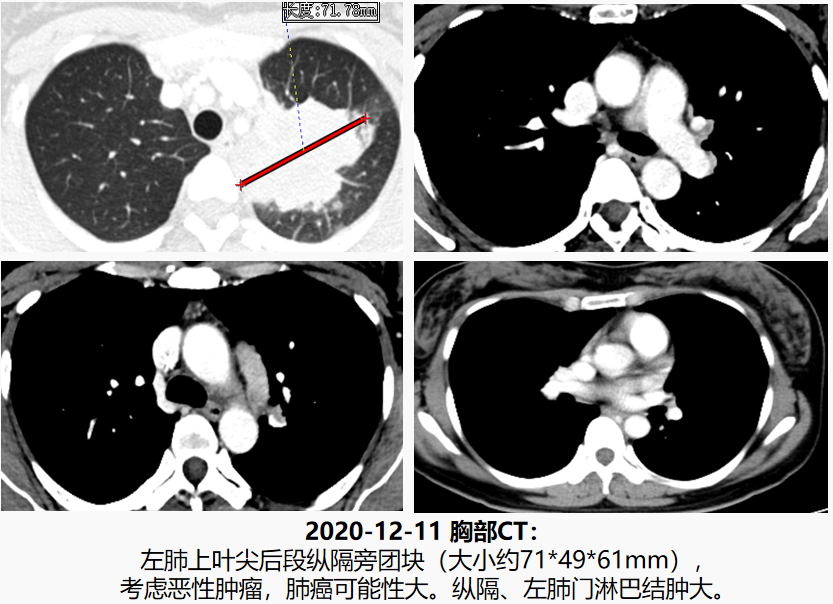

2020-12-11胸部CT:左肺上叶尖后段纵隔旁团块,考虑恶性肿瘤,肺癌可能性大。纵隔、左肺门淋巴结肿大。

放射科:左上肺占位,肿瘤分叶,内血管丰富,影像学考虑肺癌。纵隔、左肺门淋巴结肿大,考虑转移。